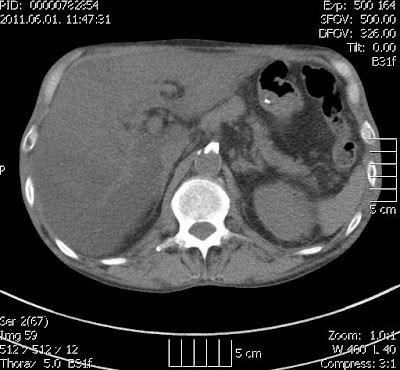

| mellkas Ct vizsgálat (hasi szelet) axialis rekon – a lig falciforme hepatis mellett egynemű, sűrű folyadék densitású képlet |